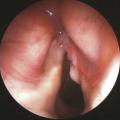

La chirurgie des cancers ORL est-elle moins mutilante qu’autrefois ?

La chirurgie des cancers des voies aérodigestives (VADS) date de plusieurs siècles. Depuis les lambeaux brachiaux de Tagliacozzi au XVIe siècle (fig. 1), elle n’a cessé d’évoluer durant les deux cents dernières années avec la progression des connaissances anatomiques, physiologiques et les avancées technologiques.